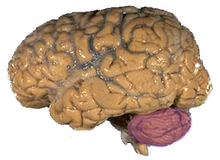

The brain of any animal is the most powerful part of the body‘The human memory can therefore be regarded as the engine of entire human and animal’s body as it controls and coordinates all the activities and functions. This is according to (Sakarya, 2007)It is also responsible of the feelings that are experienced.Cognition, which is highly correlated to brain activities, refers to a collection of mental activities such as ability to learn and understand language, reason, solve problems, attention, ability to make decisions and also memory[1] .

Brain

chimpanzee brain

According to (Blomberg, 2011), the electric activity of human brain usually starts during the late prenatal period and it is believed that at birth all the neural cells are fully developed to full number. According to neurologists,the brain is divided into three parts which are the brain stem, cerebellum and the cerebrum. According to (Finger, 2001)

Picture of the human brain showing the cerebellum painted scarlet

the cerebrum has a layer on its surface called the cerebral cortex which remains by far the largest region of the central nervous system. It is said that “cerebrum has a number of regions for the expression of behavior and emotions, movement initiation, conscious awareness of sensation and complex analysis. The highest influence to encephalography comes from electric activity of cerebral cortex due to its surface ”position”. Encephalography directly measured from the cortical surface is referred to as (electrocortiogram). Scalp recordings of randomly neuronal activity in the human brain, electroencephalography (EEG), makes it possible for recording of potential changes within a period of time between a signal electrode and a reference electrode. ‘The electroencephalography (EEG) system is comprised of electrodes, amplifiers (with appropriate filters), and a recording device for recording band frequencies’. The scalp is prepared by removing the dead skin through a light abrasion minimizing resistance as a result of the dead cells of the skin A number of numerous small pieces of electrodes are then placed on the surface of the scalp and connected to the input of the amplifier. This is according to Teplan. (2002). in his book “FUNDAMENTALS OF EEG MEASUREMENT “. The voltage between the signal electrode and the reference electrode is then amplified. During the recording process, a number of activation procedures may be used. Procedures used include closure of the eyes, lack of sleep and sleepiness, alertness and being drowsy.Neurologists note that, ‘only large number of active neurons is capable of producing electrical activity that is recordable on the surface of the head’. Electroencephalography (EEG) is very sensitive to a large number of states including state of stress, sleep, and alertness. With varying administration of stimulus, a range of frequencies of neural activity are recorded[4] [5] .